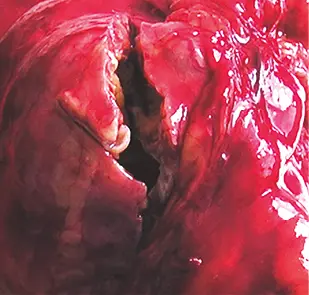

Fig: 9–b

Fig: 9–b, pieza quirúrgica la cual corresponde un Ca renal mixto: sólido–quístico.